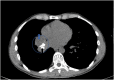

Carcinoid tumor is a neuroendocrine tumor that can arise in the bronchial tree and can be hypervascular. Here we describe a case of bronchial carcinoid tumor in a 34-year-old previously healthy male who presented with hemoptysis and right lung mass. Inspection bronchoscopy revealed bronchus intermedius endobronchial lesion and was complicated by urgent intubation and placement of endobronchial blocker for massive hemorrhage. Subsequent angiography with embolization of the bronchial artery supplying the mass resulted in control of bleeding. While massive hemorrhage has been described with biopsy of bronchial carcinoid tumor, this case suggests that careful planning for inspection bronchoscopy is needed when carcinoid tumor is suspected.